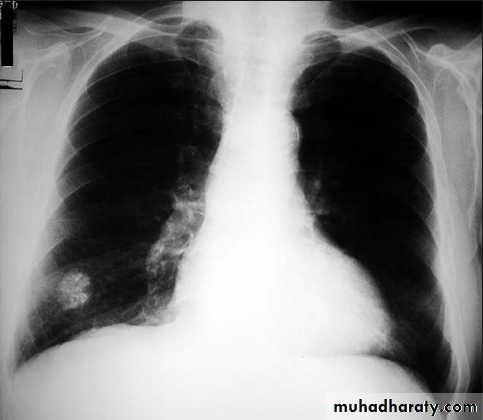

Chest X-ray shows radio-opaque (white) nodular lesion in the right mid-lung field.

Dx:x chicken pox , Histoplasmosis (calcified granuloma).